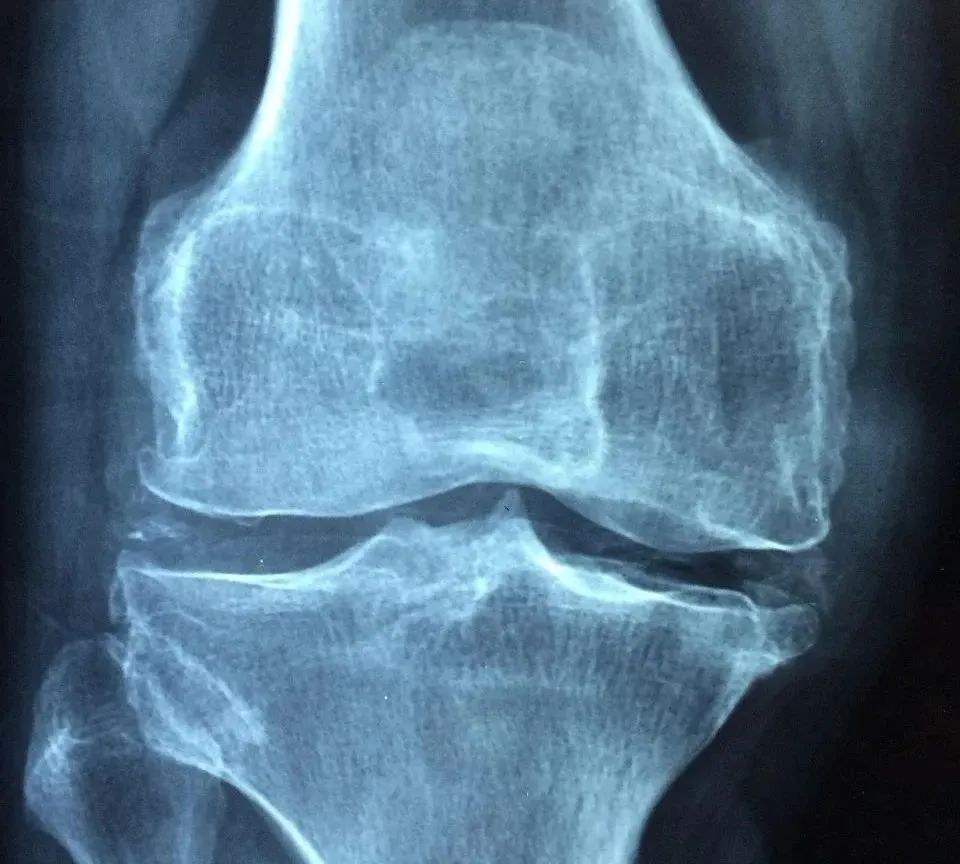

膝关节是人体最大、最复杂的关节之一,由股骨、胫骨和髌骨(也就是我们常说的膝盖骨)组成,周围有多条韧带、肌腱和肌肉共同维持其稳定性和灵活性。

膝关节的不同部位相互配合,完成走路、跑跳等多种复杂的活动。

6.关节炎

骨关节炎或类风湿性关节炎等慢性关节疾病也可能导致膝关节的稳定性下降,出现瞬间无力的情况。骨关节炎多见于老年人,而类风湿性关节炎则可发生于任何年龄段。

如果经常在走路时出现膝盖一“软”的情况,我们首先考虑半月板损伤和髌骨软化。

如果膝盖突然“软”一下的情况频繁发生,或者伴有疼痛、肿胀等症状,建议及时就医,进行详细的检查和诊断。医生可能会建议进行影像学检查以确定具体病因。